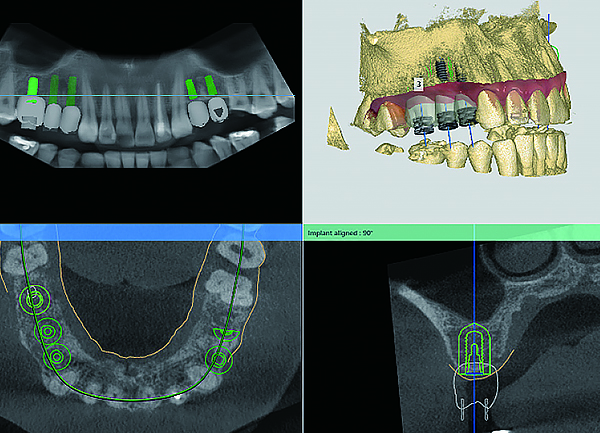

임플란트 치료를 위해 진행되는 모의 가상수술은 컴퓨터 시뮬레이션 기술을 활용하여 정밀한 치료 계획을 세우는 과정입니다. 3D CT 촬영으로 얻은 데이터를 기반으로 환자의 뼈 구조, 신경 위치, 잇몸 상태를 시각적으로 분석하며, 임플란트의 최적의 위치, 각도, 깊이를 찾아 시뮬레이션 합니다.

모의수술

정밀성과 안전성을 높이며, 치료 성공률을 극대화 합니다.

임플란트 치료를 위해 진행되는 모의 가상수술은 컴퓨터 시뮬레이션 기술을

활용하여 정밀한 치료 계획을 세우는 과정입니다. 3D CT 촬영으로 얻은 데이터를 기반으로 환자의 뼈 구조, 신경 위치, 잇몸 상태를 시각적으로 분석하며, 임플란트의 최적의 위치, 각도, 깊이를 찾아 시뮬레이션 합니다.